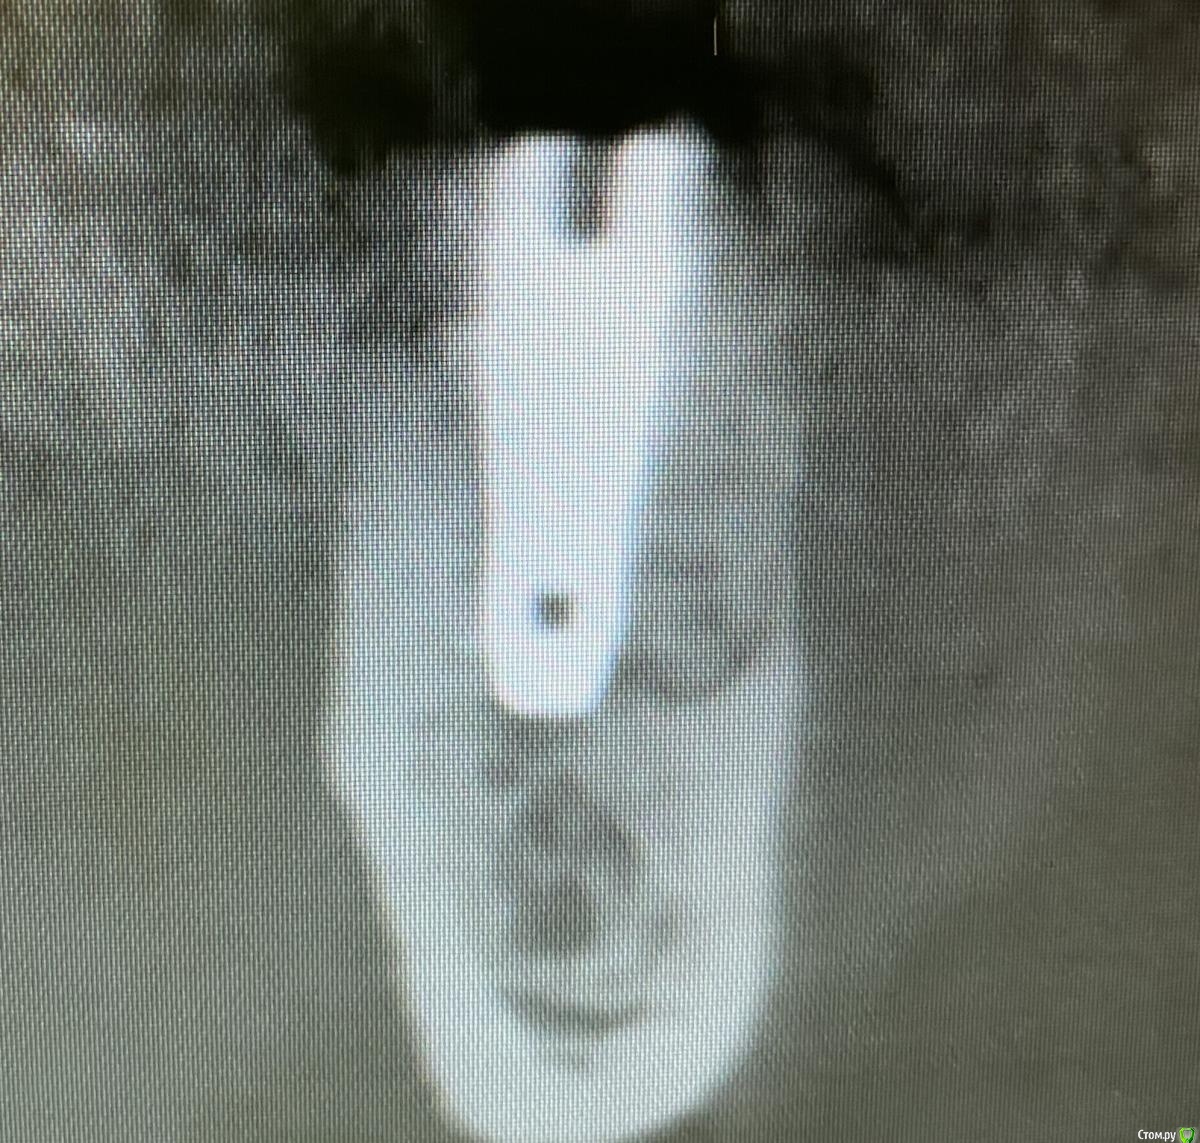

колесников Опубликовано 15 декабря, 2020 Поделиться Опубликовано 15 декабря, 2020 Про кортикалку это я предположил. Подумал что воспроизвели так же как виртуально планировали. По снимку имплант дезинтегрирован. Я бы заменил одномоментно на другой или через консервацию,как пациент настроен. 1 Ссылка на комментарий

Bier Опубликовано 16 декабря, 2020 Поделиться Опубликовано 16 декабря, 2020 @Bier, Олег Юрьевич, скажите пожалуйста, что думаете? @колесников, ваше мнение тоже интересует. (простите не знаю как ваши ИО ) Там на лицо резорбция вокруг имплантата. Я за удаление. Ссылка на комментарий

BORA Опубликовано 18 декабря, 2020 Поделиться Опубликовано 18 декабря, 2020 Есть вероятность,что резорбция в последующий месяц может увеличиться и появится фенестреция вестибулярной стенки(возможно она уже есть,маленькая).В связи с этим вариант с одномоментной имплантацией ,проводить нежно и точно,выскоблив и вестибулярно добавить кости.Следующий лучший вариант,консервация и тоже вестибулярно докинуть кости. Ссылка на комментарий

колесников Опубликовано 18 декабря, 2020 Поделиться Опубликовано 18 декабря, 2020 Вот аналогичный случай. Только в Вашем варианте импланта,я бы загубил его Ссылка на комментарий